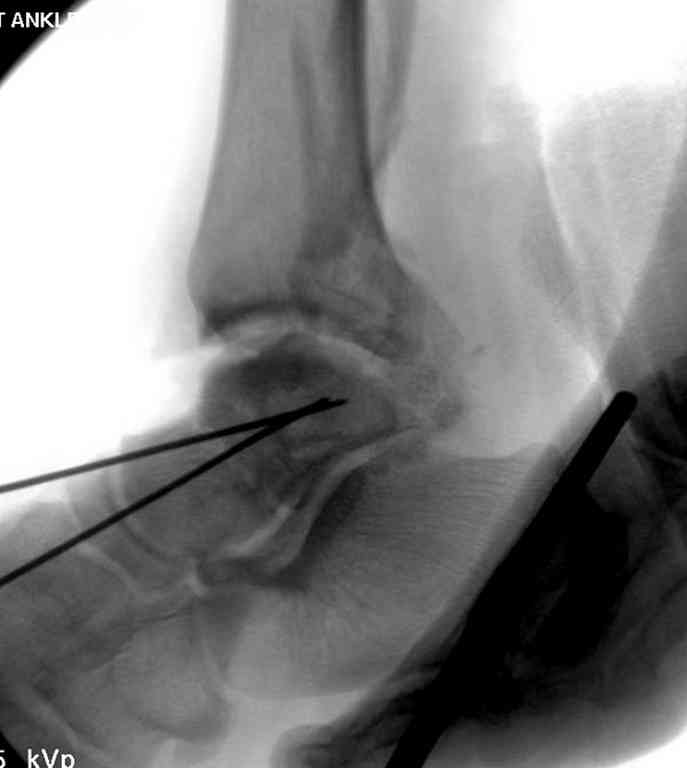

Второй случай прооперирован вчера.

10 дней назад поступил с открытым повреждением медиальной лодыжки и переломо вывихом таранной кости. Ургентно сделана репозиция с наложением наружного фиксатора + Irrigation&Debridment.

Во время репозиции выявили повреждение заднего сухожилия м. тибиалис и задней большеберцовой артерии. Медиальную рану удалось закрыть частично и установлен вакуум.

Дважды провели Irrigation&Debridment с заменой вакуума.

Вчера провели фиксацию.

Из-за многооскольчатости дистальной части малоберцовой, где невозможно было провести фиксацию шурупами, перелом зафиксирован подпирающей пластиной, которая должна служить дополнением отсутствующей дистальной части малоберцовой (lateral cortex substitute).

Для стабильности два шурупа на синдесмоз.

Медиальную рану с приближенными краями продолжаем вакуумировать (KCI). Наружный фиксатор оставлен на пару недель, надеюсь, небольшая рана будет гранулировать и закроется без кожной пластики. Фиксация медиальной ложыжки не планируется.